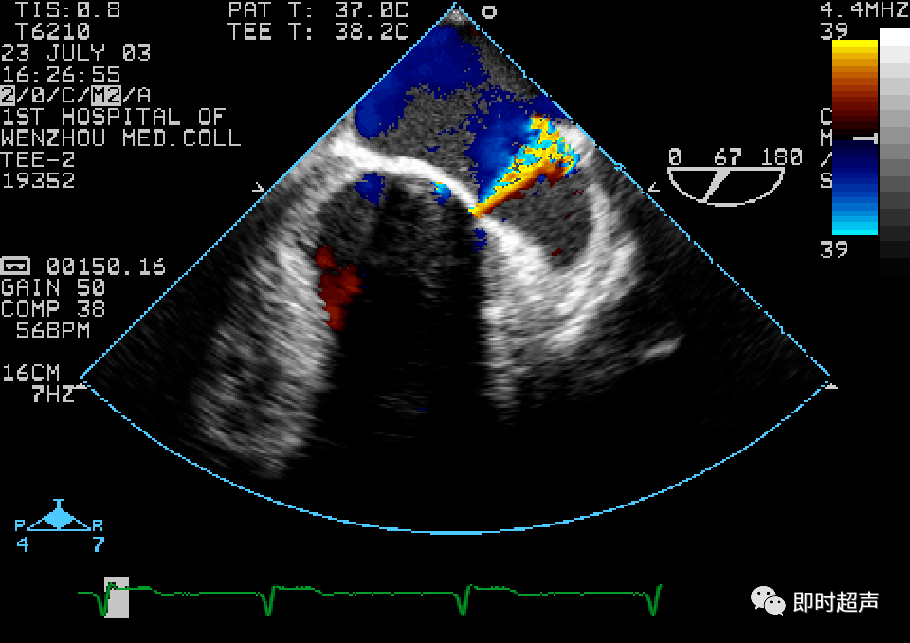

成功捕捉二尖瓣前叶a2和后叶p2,经超声心动图反复确认瓣叶夹持牢固后